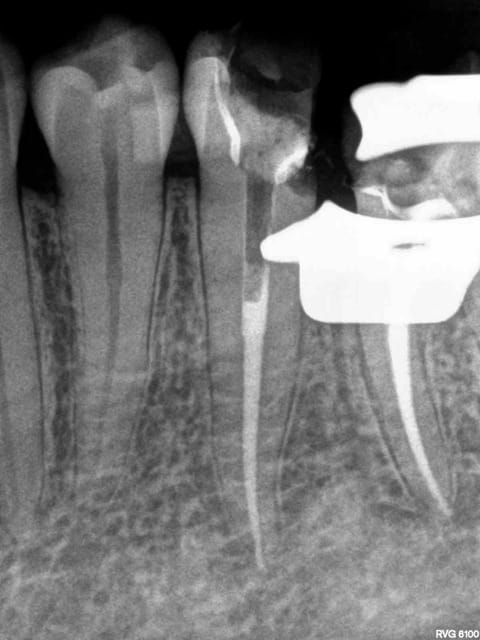

Post de depart !

Honnêtement, la dent est quand même bien niquée !

Fêlure mesiale et distale, le curetage n'est pas complet sur l'arrête restante.

Une couronne, c'est pas une connerie, patient 25-35 on tente l'onlay, patient 45-55, je couronne directement !

C'est une 6 ! 150 kg pression au cm2 !